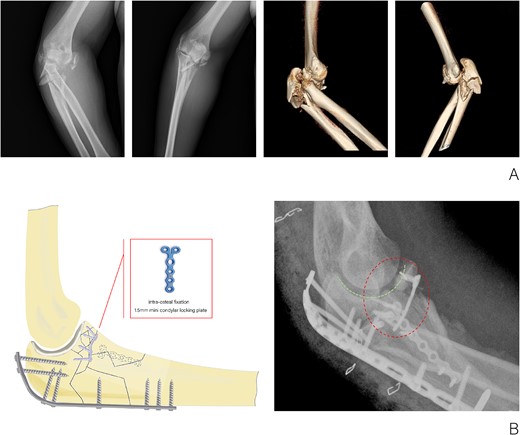

(A) X-ray and CT three-dimensional reconstruction examination of elbow fracture. (B) Diagram of intra-osteal fixation of comminuted coronoid process fracture with mini plate and postoperative X-ray examination of the elbow.

The surgical procedure was conducted under a combination of brachial plexus block anesthesia and general anesthesia, with the application of an upper arm tourniquet. A posterior cubital incision was made to access the fracture and safeguard the ulnar nerve. The primary fracture fragments of the coronoid process measured 8 × 9, 15 × 9, and 10 × 9 mm2, respectively. A three-hole, 1.5-mm mini condylar locking plate and a 1.0-mm Kirschner wire were utilized to stabilize the coronoid process in conjunction with the olecranon intra-osteally, aiming to reconstruct the joint surface. A proximal dorsal ulna locking compression plate was employed to secure the olecranon to the distal ulna from the dorsal aspect. Additionally, a large medial fracture block of the proximal ulna was stabilized using a six-hole, 1.5-mm mini condylar locking plate. Subsequently, the radial head was exposed and its fracture was stabilized with a 2.0-mm cannulated screw. The elbow drawer test and stress test results were negative, suggesting the absence of instability related to injuries of the medial and lateral collateral ligaments and the anterior capsule. Consequently, exploration of the collateral ligaments was deemed unnecessary and external fixation of the elbow was not performed. The duration of the surgical procedure was approximately 100 min.